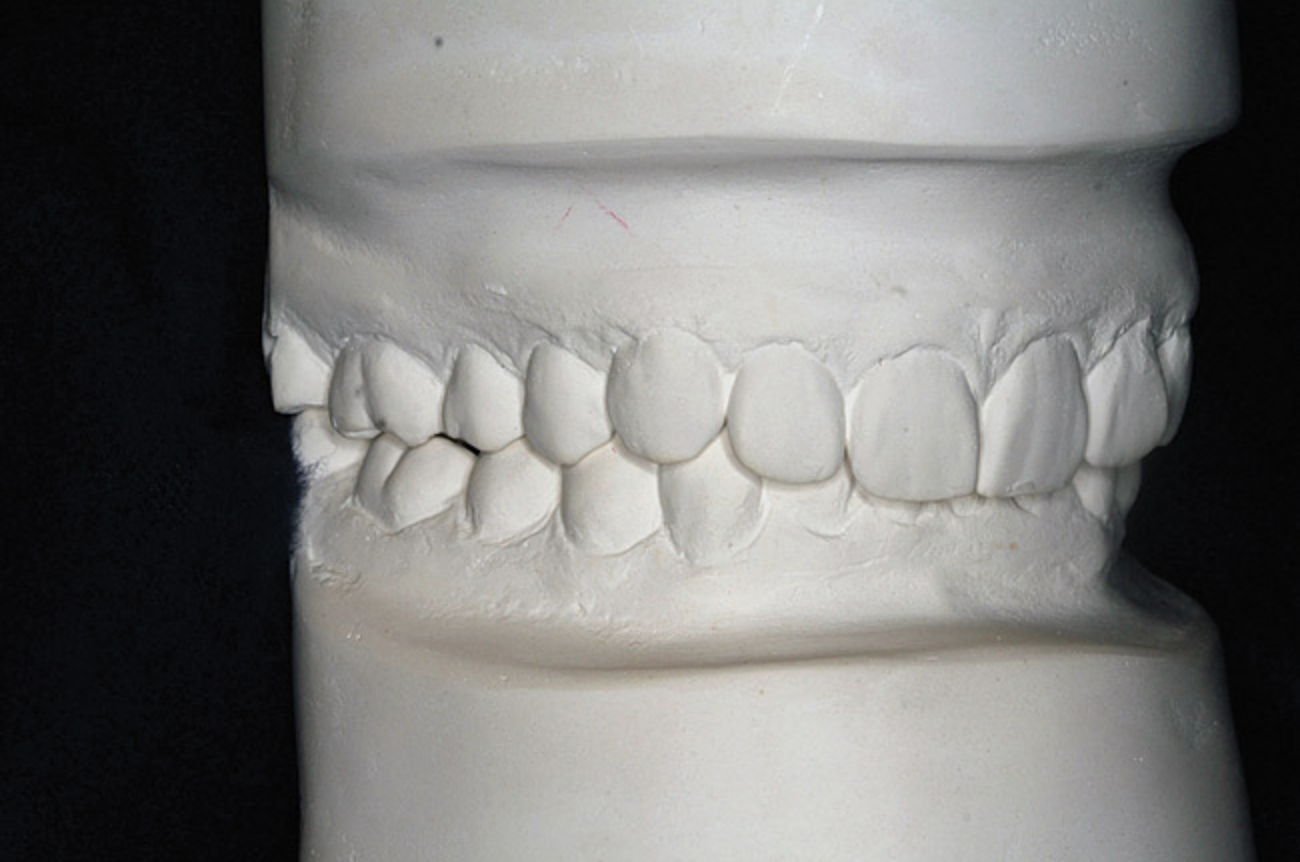

A stable TMJ is critical in establishing a normal functional occlusion. Unless the condyles are in a stable musculoskeletal position, there are always interferences to normal function and stress placed on the masticatory system.1-3,15 In orthodontics, the Angle classification of malocclusion using handheld models has been the standard to evaluate the fit of the teeth. However, it is not possible to truly identify the occlusion/malocclusion using handheld models. Before the occlusion can be evaluated, the clinician must ascertain the joint position and condition (Figure 7 and Figure 8).1,16

Figure 7A  This case is an example of the importance of evaluating the bite with the joints seated in a stable position. Orthodontic treatment was rendered to correct a

Figure 7A

Figure 7B  This case is an example of the importance of evaluating the bite with the joints seated in a stable position. Orthodontic treatment was rendered to correct a

Figure 7B

Figure 7C This case is an example of the importance of evaluating the bite with the joints seated in a stable position. Orthodontic treatment was rendered to correct a

Figure 7C

Figure 7D  This case is an example of the importance of evaluating the bite with the joints seated in a stable position. Orthodontic treatment was rendered to correct a

Figure 7D